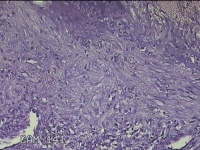

左卵巢囊肿

性别

女

年龄

47岁

临床诊断

左附件囊肿

一般病史

不规则阴道流血20余天。

标本名称

大体所见

灰白暗红色囊壁样组织4.3x1.3x0.3cm一块,表面光滑,因已切开,囊内容物已流失,囊壁厚0.1cm。

良性病变。